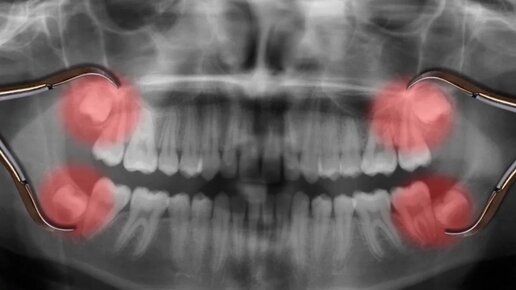

Под восьмерками понимаются так называемые «зубы мудрости», которые появляются позже всех остальных зубов. У стоматологов до сих пор нет единого мнения относительно их судьбы. Одни считают, что лучше их удалить, причем чем раньше, тем лучше, а другие уверяют, что их надо непременно сохранить. Что же делать с восьмерками и как это повлияет на внешность и здоровье, aif.ru рассказала директор детской стоматологической студии, врач-стоматолог Виктория Шелудкова. Что мы знаем о третьих постоянных молярах,...